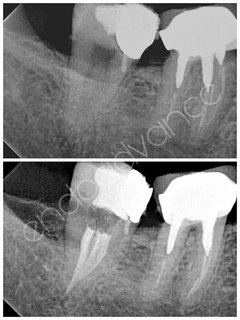

Αρχική ενδοδοντική θεραπεία σε άνω γομφίο με περίπλοκη ανατομία